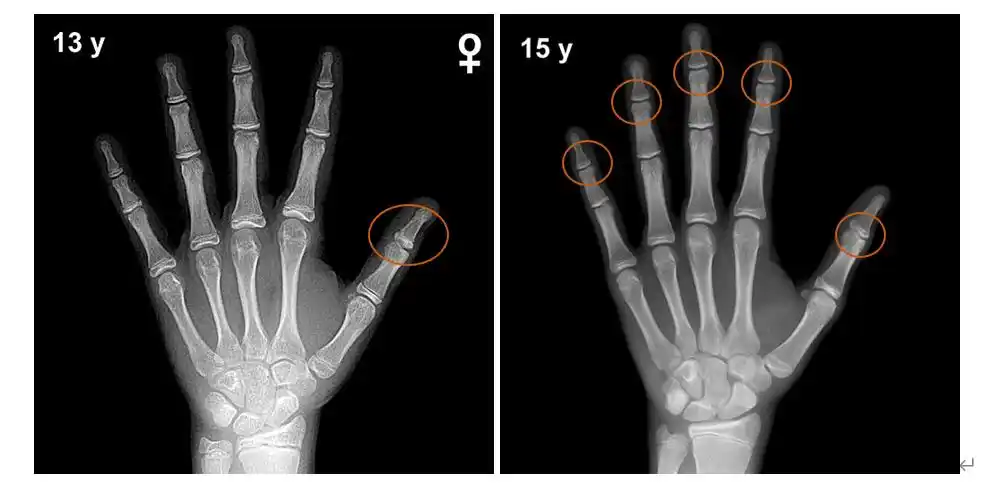

(开始闭合的骨骺.